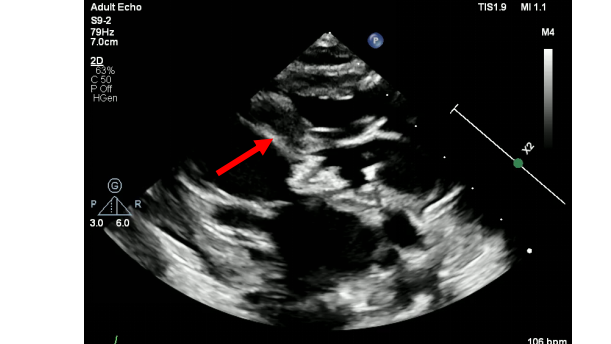

一例产前重度主动脉瓣狭窄的艰难治疗历程

2025儿科最佳临床实践上海交通大学医学院附属新华医院儿童心脏中心团队分享主讲嘉宾:李文娟 副主任医师点评嘉宾:陈笋 主任医师上海交通大学医学院附属新华医院儿童心脏中心创建于上世纪70年代,是国内最早开展小儿先天性心脏病诊治的临床专科。在老一辈专家刘薇廷教授、丁文祥教授的带领下,发展为集医、教、研一体的国内一流的小儿心脏病诊疗中心。本科室是上海市高教局重点学科、上海市医学领先学科、上海市首批小儿心血管临床医学中心,国家级继续教育中心和教育部国家重点学科儿科学的主要组成部分,先后承担并完成了科技部十五攻关项目、863计划、973子项目、国家自然科学基金等数十项课题,荣获国家、省市级科技进步二、三等奖、中华医学奖三等奖、宋庆龄儿科医学奖等十余项。科室品牌特色:1、强大的儿科和强大的产科催生出强大的围产医学。2、具有最优结构的“立体化”儿童心脏中心融。3、内外科融合治疗复杂先天性心血管疾病。4、围产医学背景下的先心病一体化治疗。5、巅峰领域先行者——宫内介入治疗。